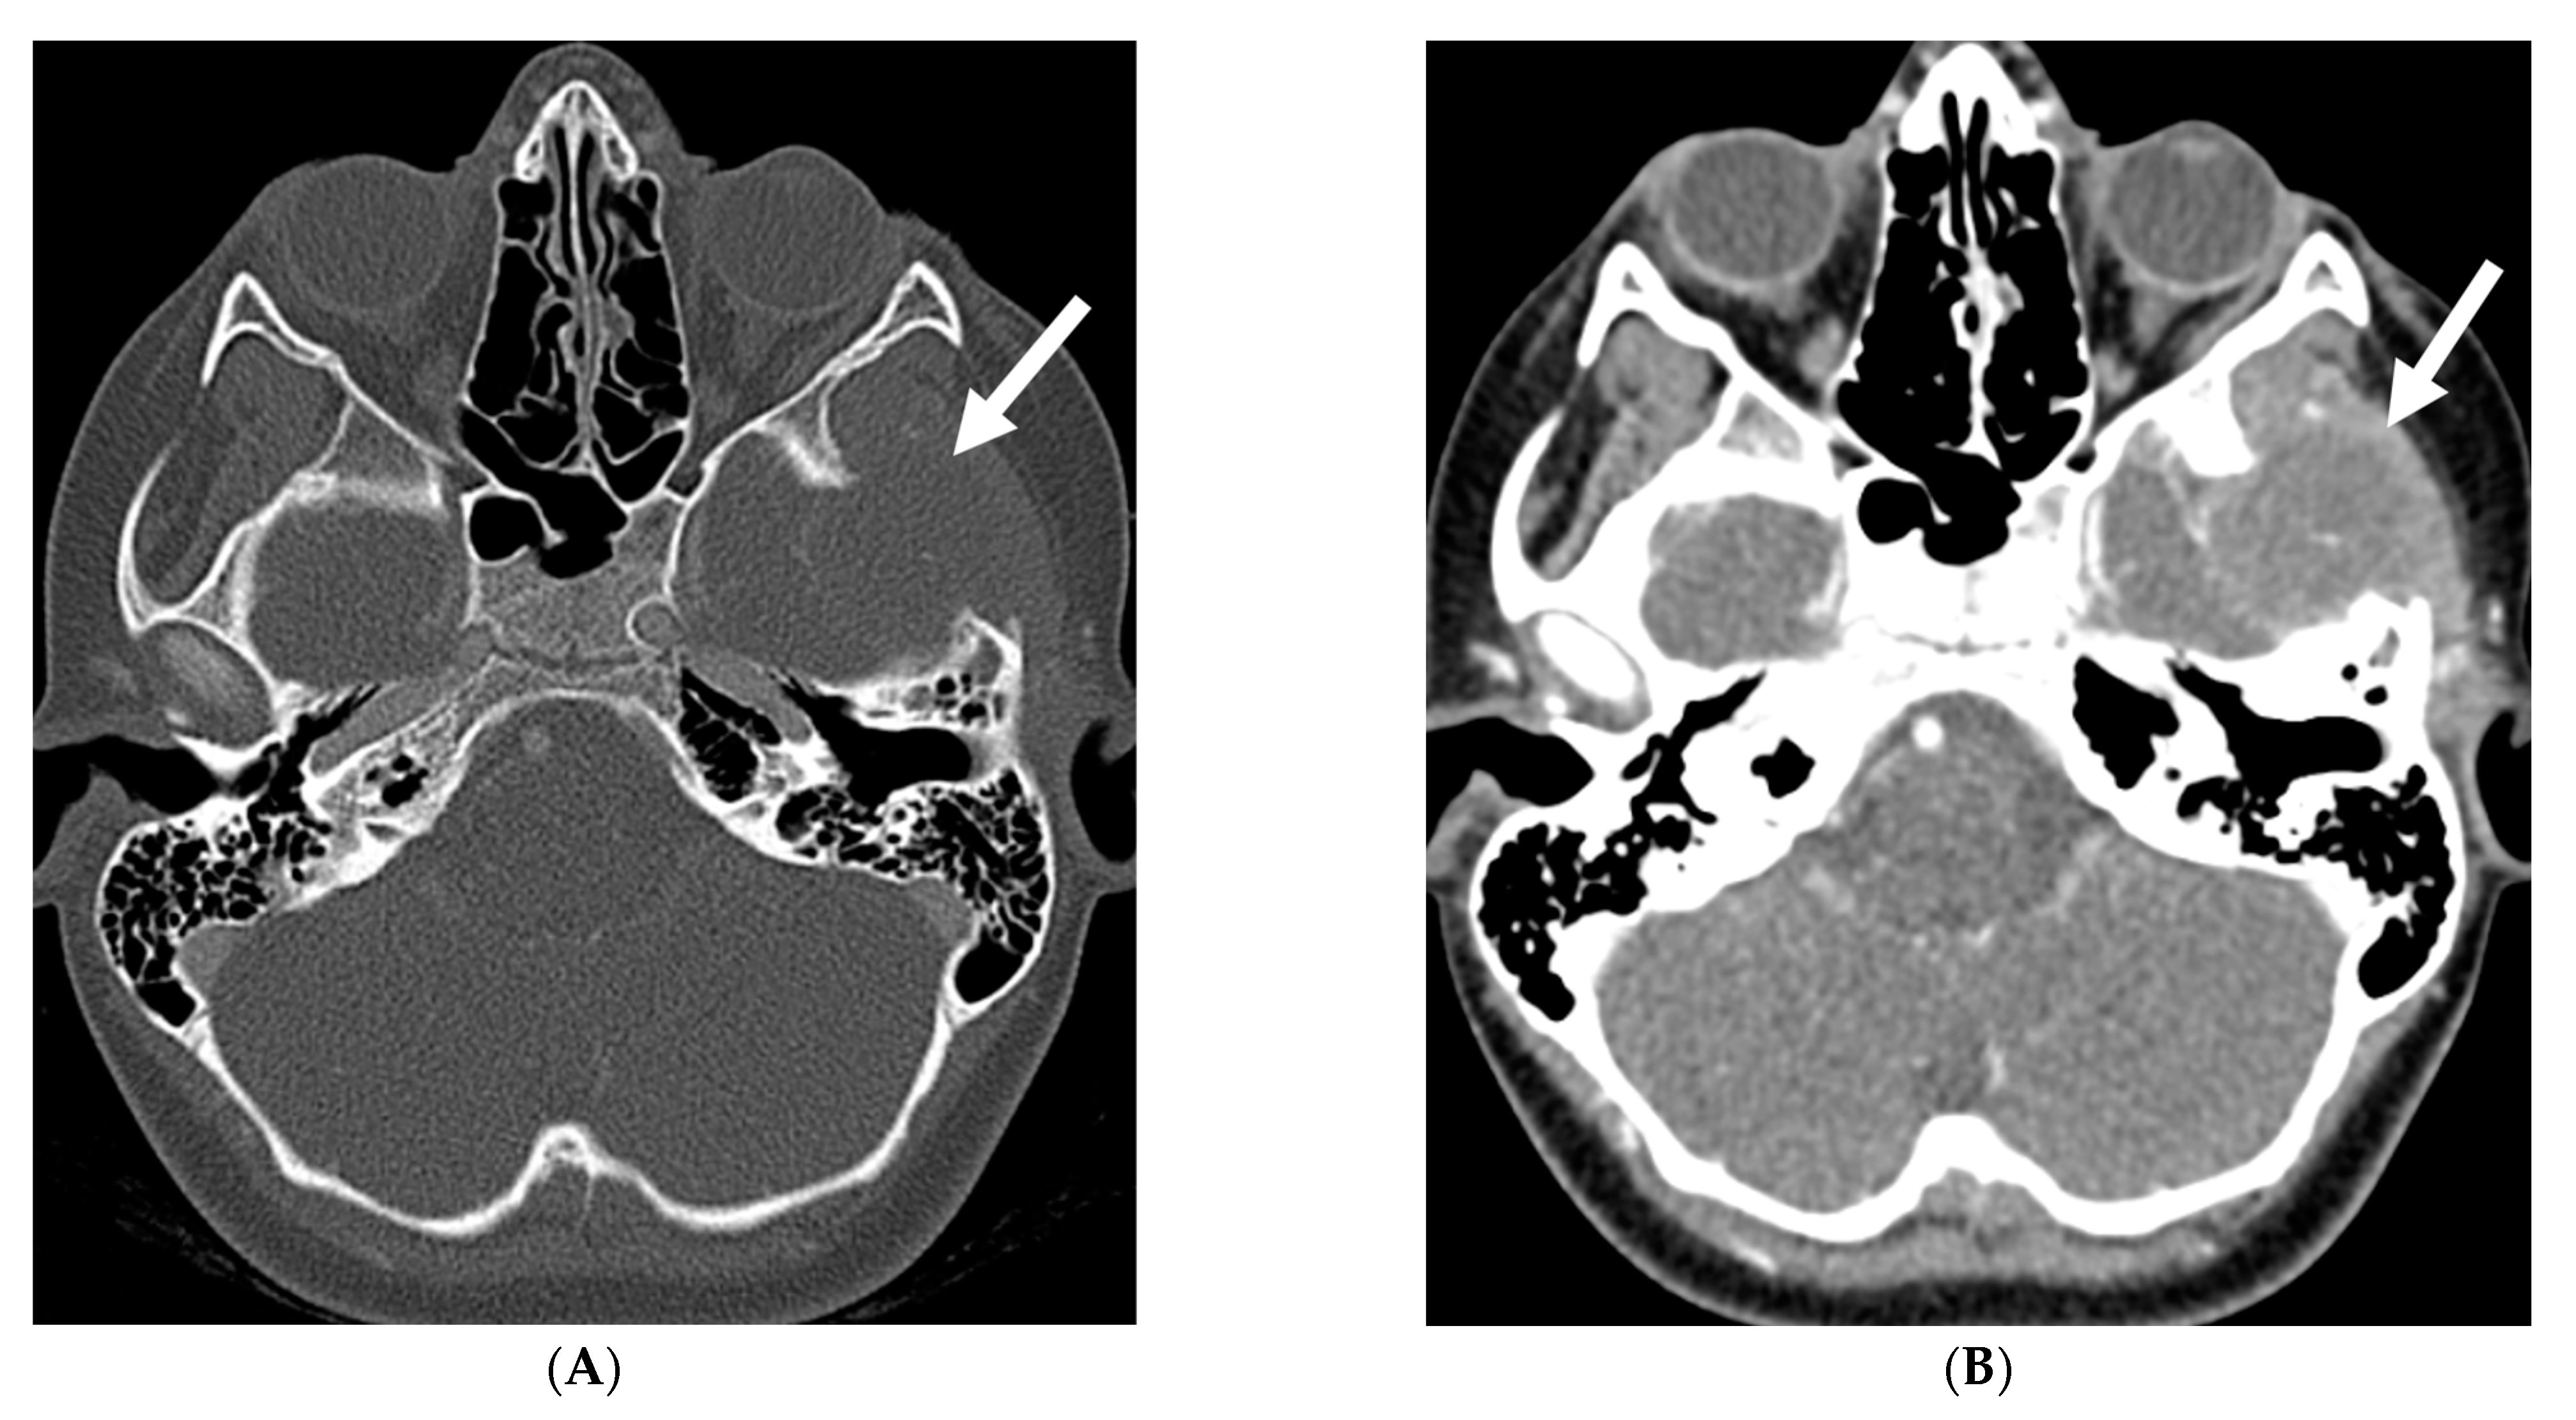

With regard to spine imaging, in addition to the intracranial features of dural enhancement, venous engorgement and subdural collection, unique findings include meningeal diverticula, dural ectasia and C1–C2 sign (Figure 8 and Figure 9). Additionally, a CT myelogram may identify the precise location of the CSF leak which can be sealed off with a blood patch [65,68].

Figure 8.

Sagittal T1 (A), post axial T1 (B,C), axial CT myelogram (D) and technetium 99 m DTPA SPECT-CT (E): 16-year-old with Gorham’s disease. There is cerebellar tonsillar herniation and decrease in prepontine cisterns (white arrows). Significant increase in the size of the venous sinuses (dashed arrow). Diffuse pachymeningeal enhancement is seen (black arrows). Cystic-appearing foci at the skull base are in keeping with lymphangiomatosis with contrast pooling into the lytic lesion (curved arrow). Abnormal radiotracer extravasation in the left clival region correlating with lytic lesion (open arrow). Features are in keeping with intracranial hypotension secondary to CSF leak.

Figure 9.

Sagittal T2 FS (A), sagittal (B) and axial (C) T1 post contrast: 3-year-old with neck pain post LP. There is diffuse epidural thickening, with increased T2 signal and enhancement, throughout the cervical, thoracic and lumbar spine (white arrows). Several prominent flow voids are seen within the anterior epidural thickening in the upper cervical region (dashed arrow). There is also increased high T2 signal between the occiput and posterior arch of C1, and between the posterior arch of C1 and spinous process of C2 (curved arrows) in keeping with “C1–C2 sign”. Findings are related to intracranial hypotension post lumbar puncture.